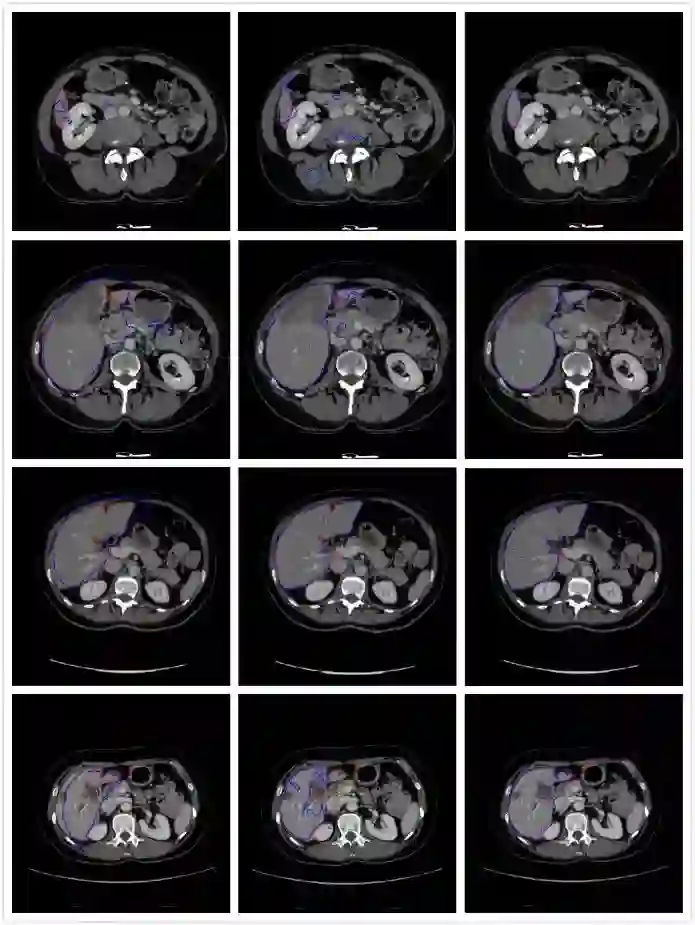

• 结果对比:本文算法对于各种形状的肝脏都有较高的分割准确率;FCN-8s对肝脏区域较大的图像分割准确率高,但结果较为细碎,分割较小的肝脏时,有许多冗余部分;U-Net能分割出肝脏所在区域的大致位置,但是无法获得肝脏的精确边界。

(a) U-Net分割图   (b) FCN-8s分割图 (c) 本文算法分割图

图3 不同算法分割图(注:红色轮廓为Ground Truth,蓝色轮廓为最终分割结果)